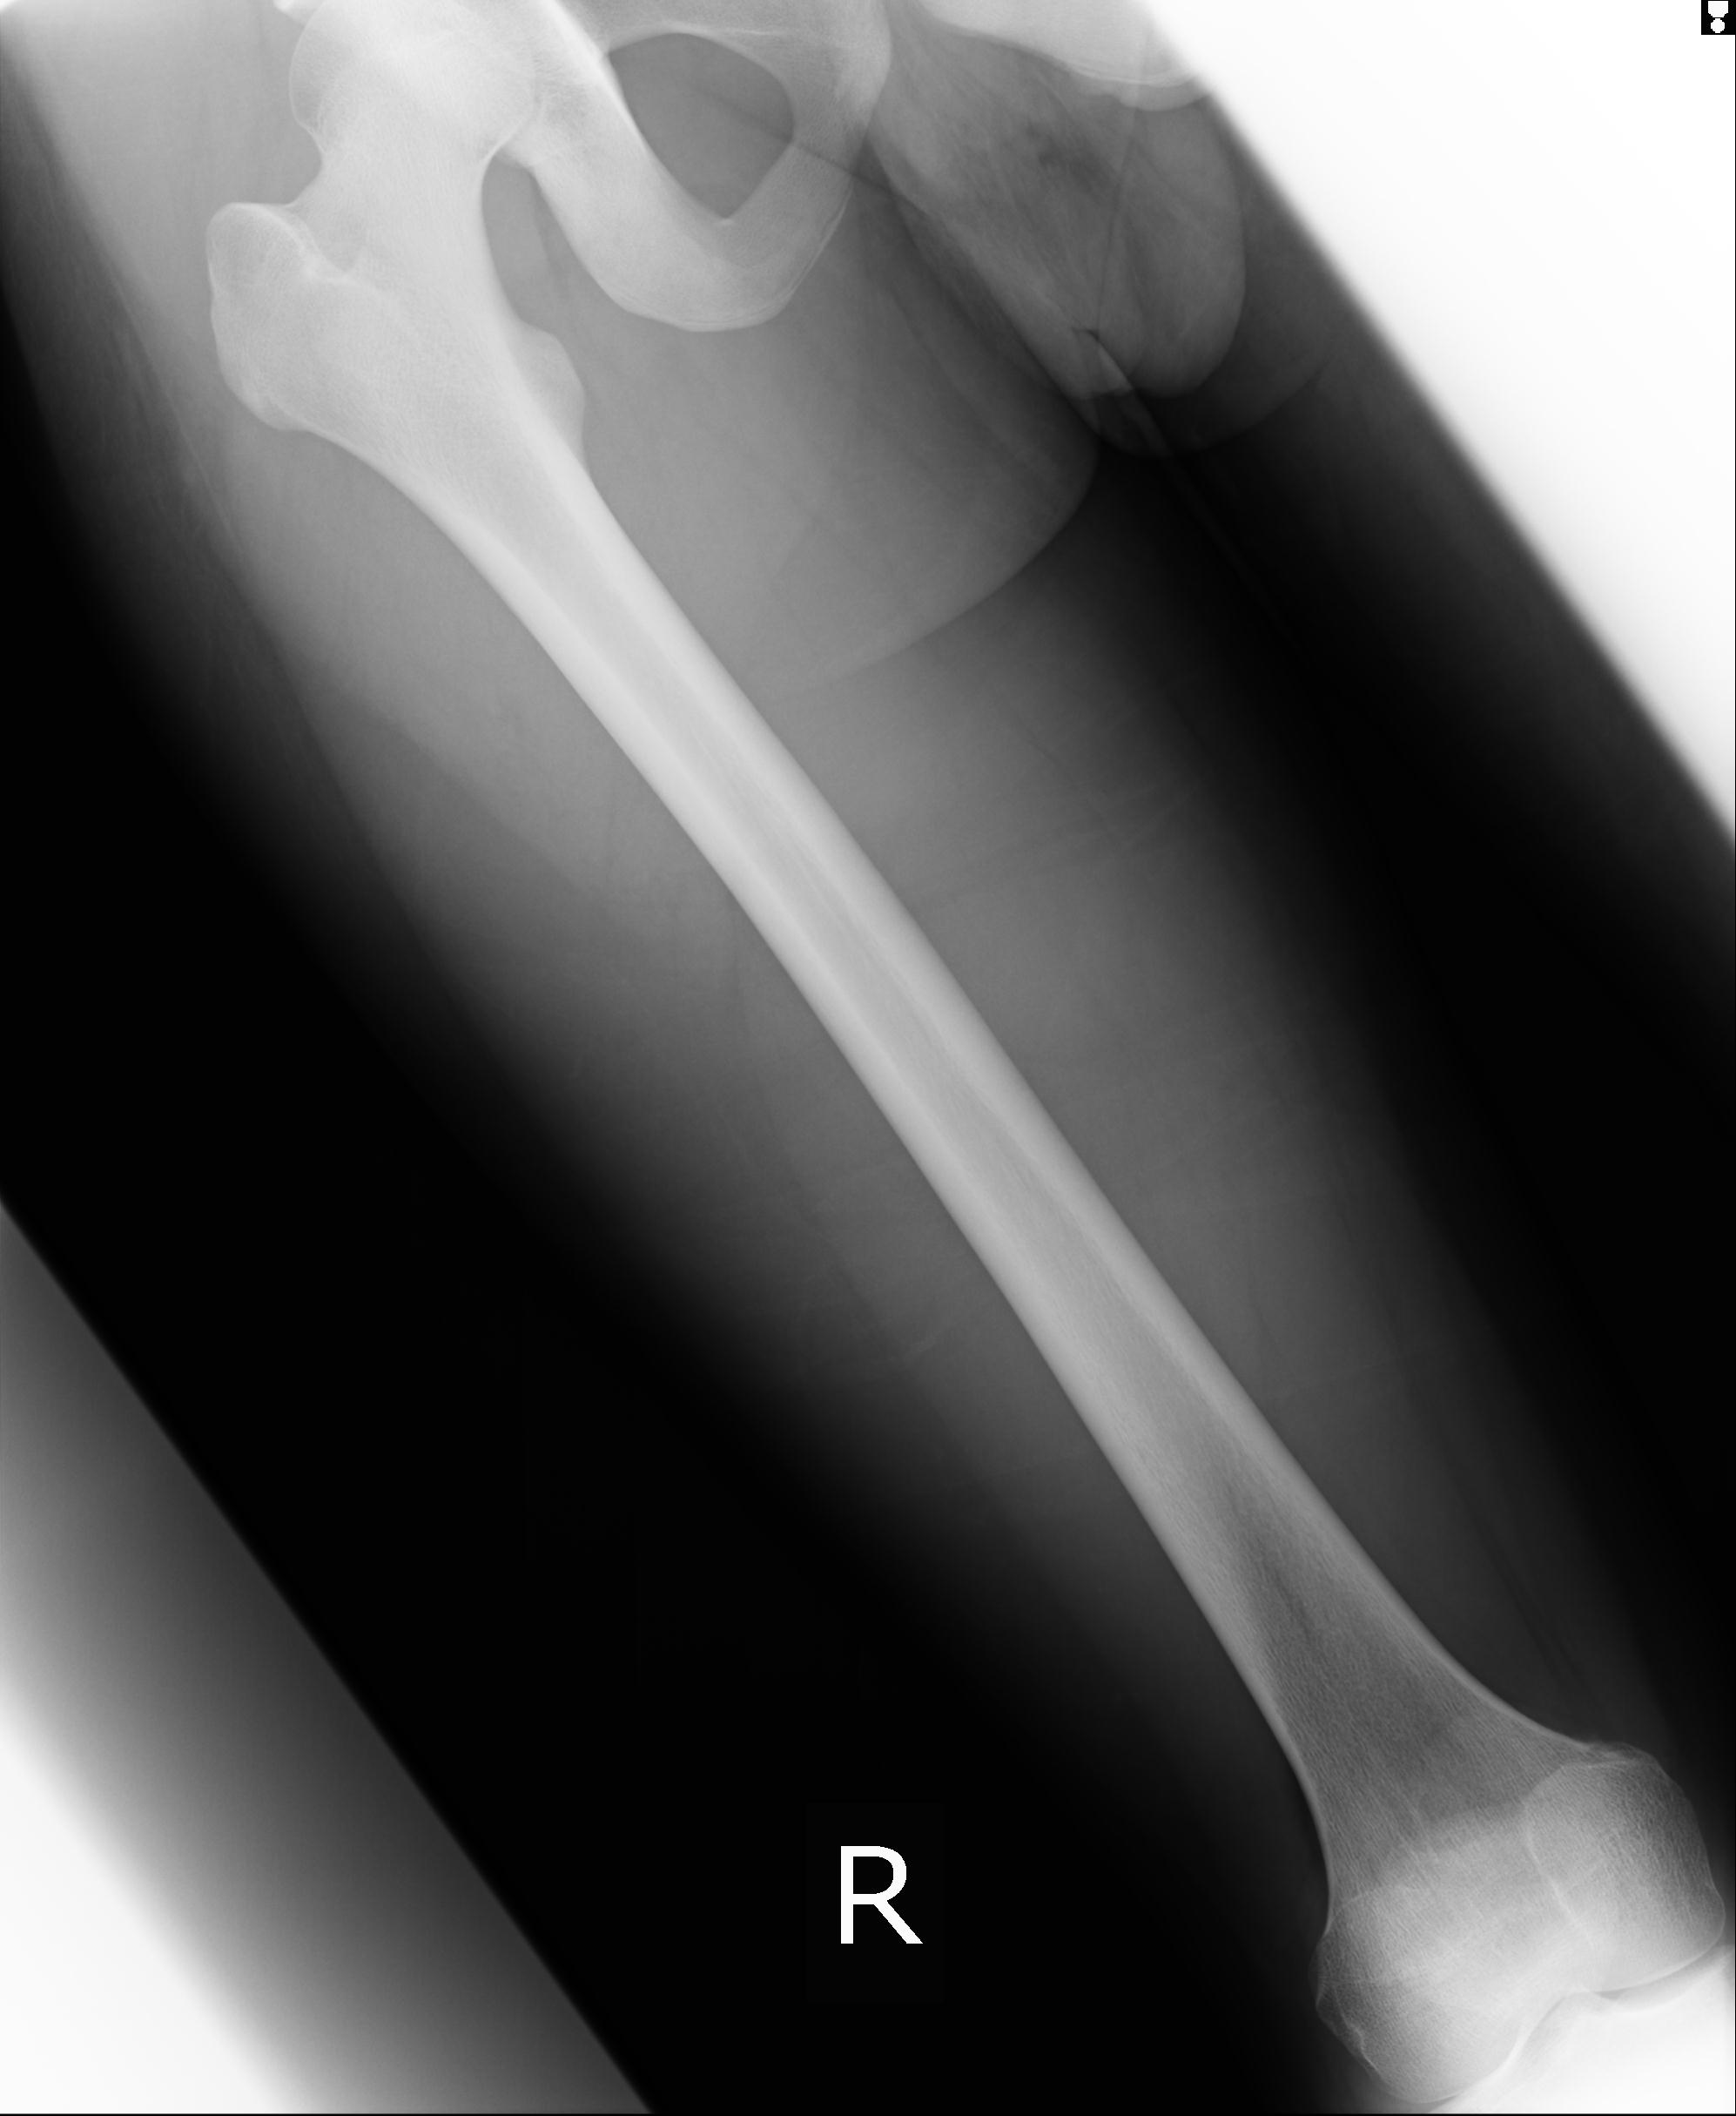

46666 1/23 両股正面+軸と右手関節 2R 76歳女性 右橈骨遠位端

46666 1/28 両股正面+軸と 1/26 右手関節 2R 76歳女性 右転子部骨折